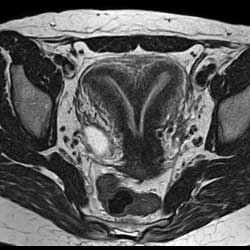

8 .盆腔病变: MRI 多方位、大视野成像可清晰地显示盆腔的解剖结构。尤其对女性盆腔疾病具有重要诊断价值,对盆腔内血管及淋巴结的鉴别较容易,是盆腔肿瘤、炎症、子宫内膜异位症、转移癌、前列腺癌等病变的最佳影像学检查手段。